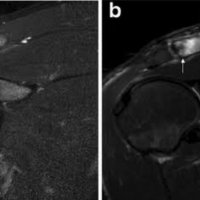

MRI is far more sensitive to detect DCO in an early stage. The most common MR-finding is bone marrow oedema in the distal clavicle, sometimes also in the articular part of the acromion, but less distinct.

Often, a hypointense line is seen in this area of clavicular bone marrow oedema, representing a subchondral fracture. AC-joint abnormalities are common, and include effusion, mild widening, intra-articular bone fragments and capsule hypertrophy. Other MR-findings are similar to those seen on radiographs, as described above.